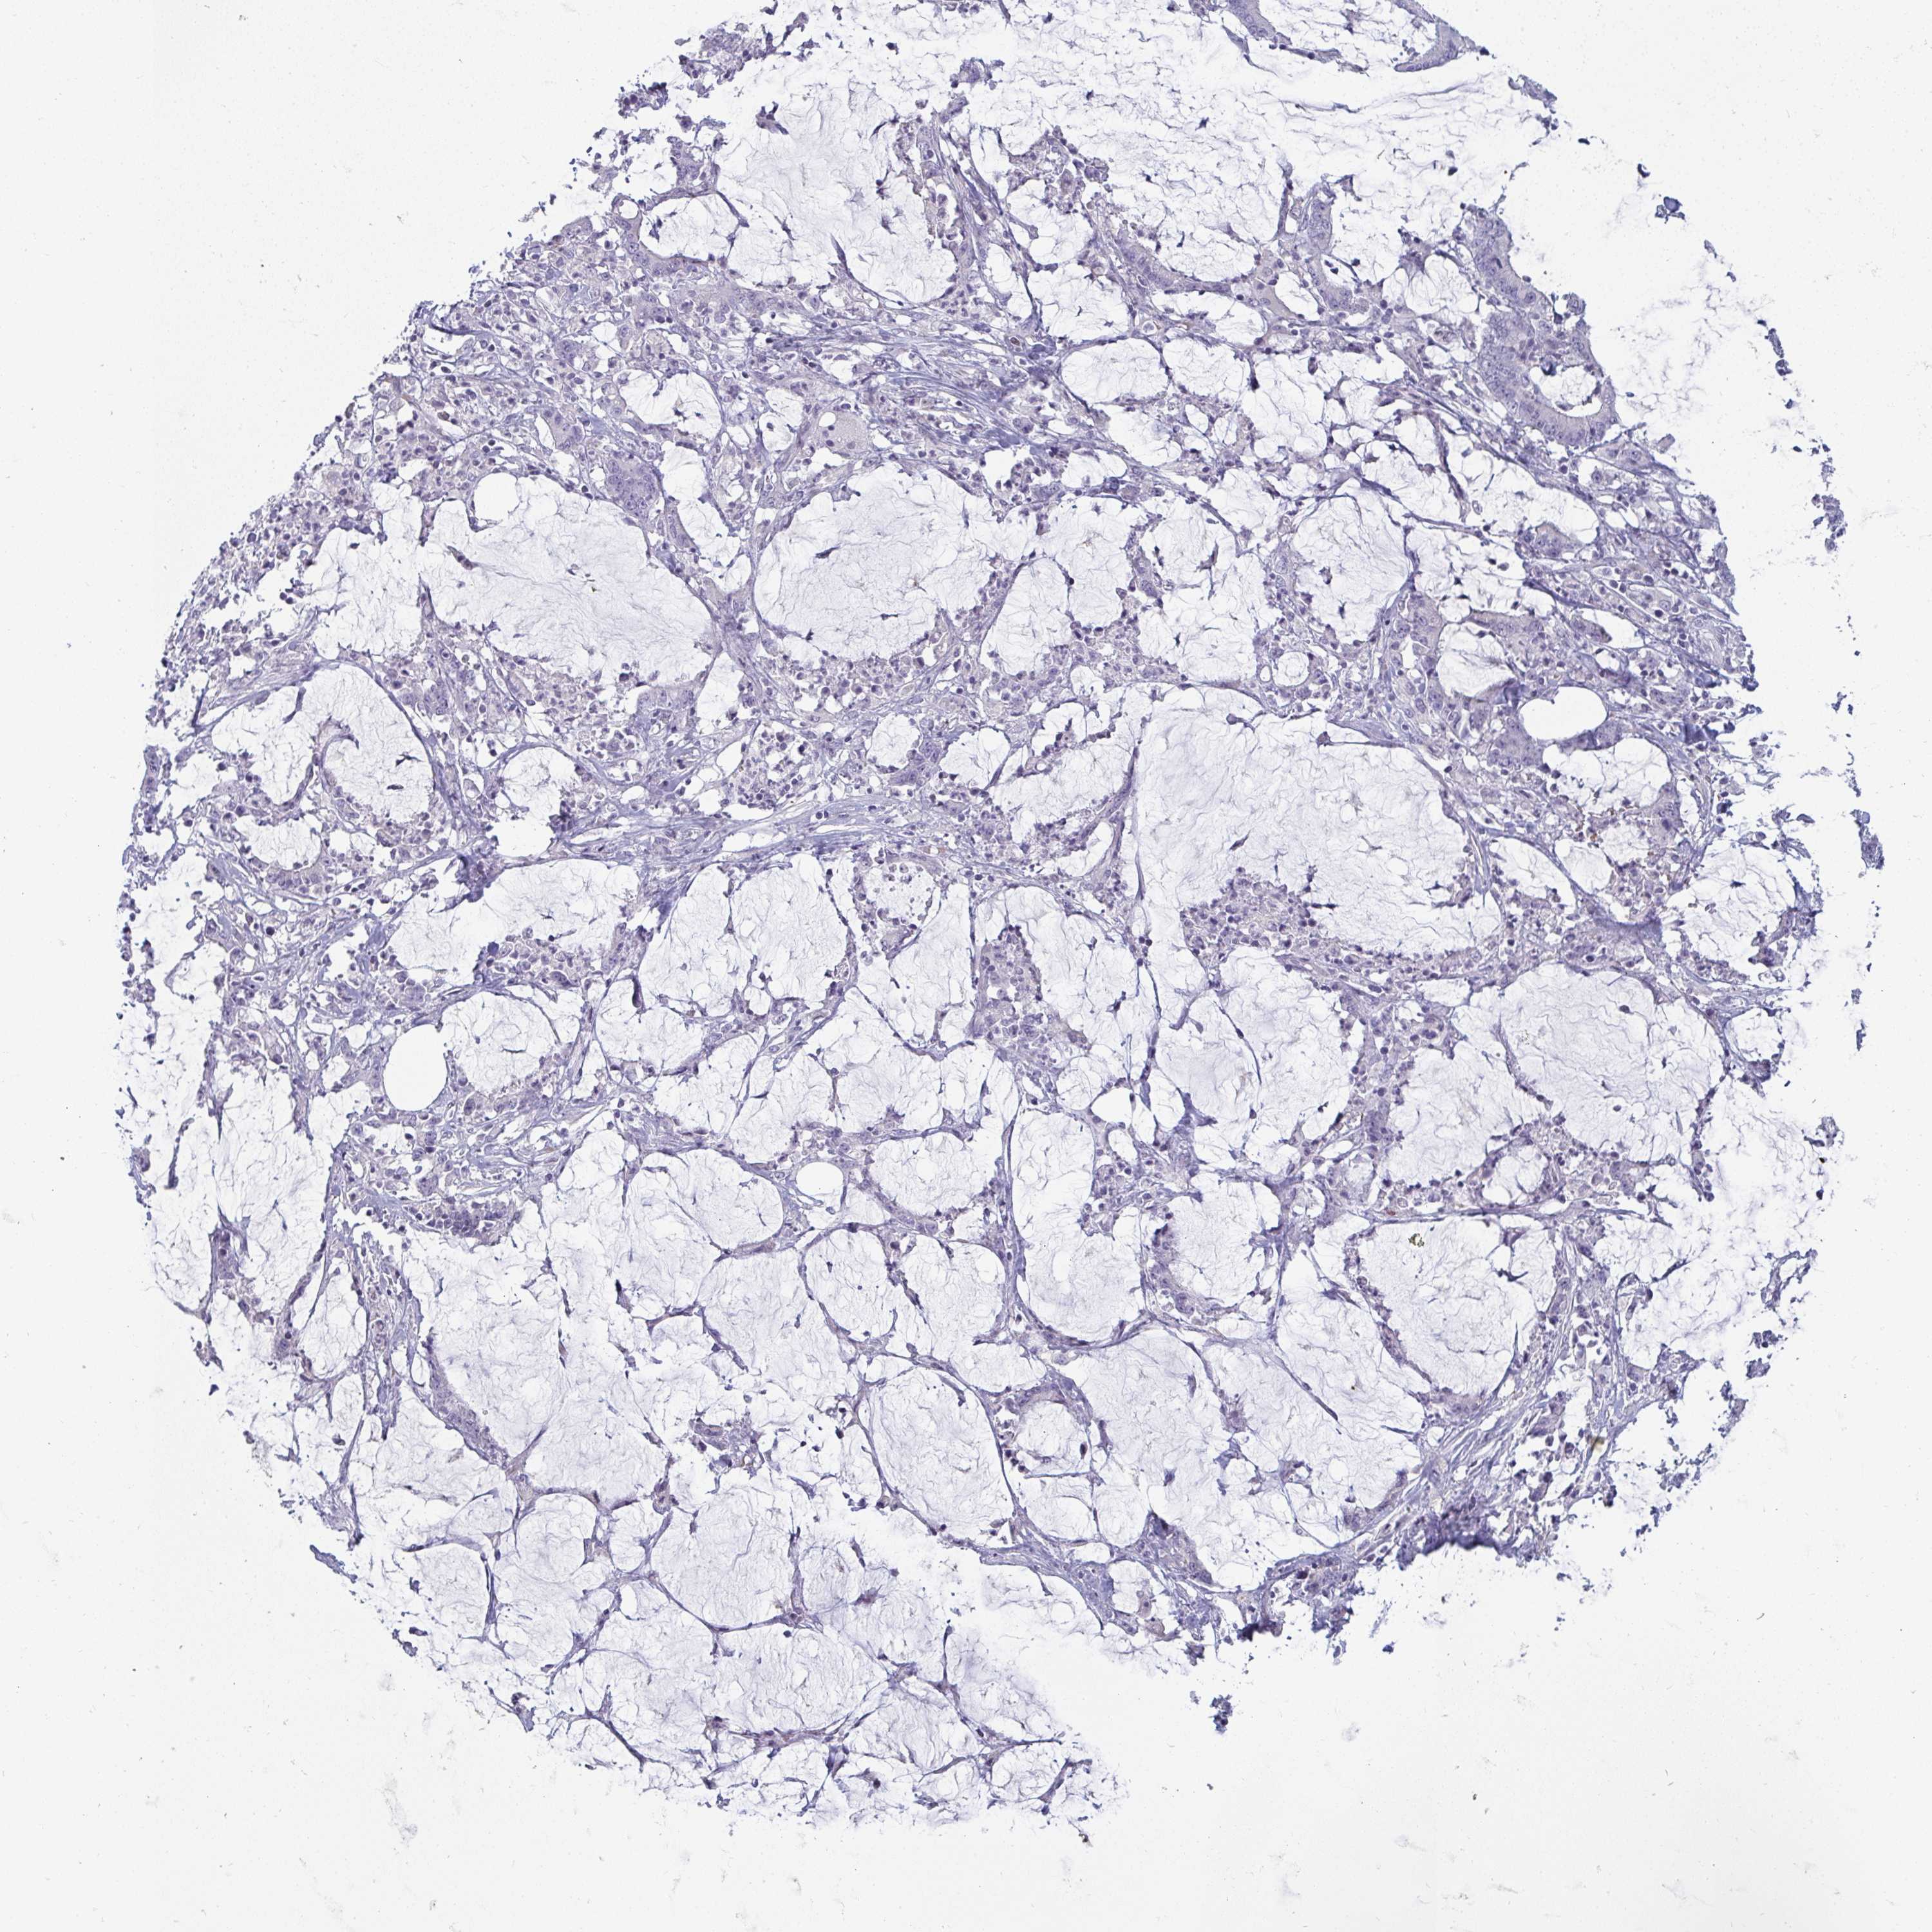

STOMACH CANCER - Protein expressioni

A mouse-over function shows sample information and annotation data. Click on an image to view it in a full screen mode. Samples can be filtered based on level of antibody staining by selecting one or several of the following categories: high, medium, low and not detected. The assay and annotation is described here.

Note that samples used for immunohistochemistry by the Human Protein Atlas do not correspond to samples in the TCGA dataset.

Antibody stainingi

Antibody staining in the annotated cell types in the current human tissue is reported as not detected, low, medium, or high, based on conventional immunohistochemistry profiling in selected tissues. This score is based on the combination of the staining intensity and fraction of stained cells.

Each image is clickable and will lead to virtual microscopy that enables deeper exploration of all samples and also displays staining intensity scores, fraction scores and subcellular localization as well as patient and tissue information for each sample.

Antibody HPA049911

Antibody CAB010161

Staining

High

Medium

Low

Not detected

Intensity

Strong

Moderate

Weak

Negative

Quantity

>75%

75%-25%

<25%

None

Location

Nuclear

Cytoplasmic/membranous

Cytoplasmic/membranous,nuclear

Adenocarcinoma, NOS